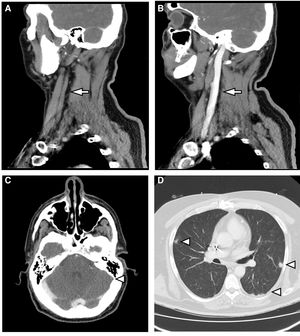

A) Reconstrucción sagital de TCMD con contraste intravenoso. Ausencia de flujo en la vena yugular interna izquierda (flecha). B) Se compara con la vena yugular interna contralateral bien replecionada (flecha). C) TCMD con contraste intravenoso. Ausencia de flujo en seno sagital (punta de flecha). D) TCMD con ventana de pulmón. Se observan múltiples nódulos parenquimatosos de distribución periférica (puntas de flecha).

Se trata de un varón de 46 años hospitalizado para estudio de dolor torácico con antecedente de infarto agudo de miocardio hacía 6 meses y colocación de DAI por vía subclavia izquierda 2semanas antes del presente ingreso. El segundo día de hospitalización presentó episodio de fiebre de 39°C asociado a flebitis en vía venosa periférica. Se inició tratamiento con amoxicilina-clavulánico, pasando tras la primera dosis a 2g de cloxacilina intravenosa cada 6/h al objetivar en 2/2 hemocultivos crecimiento de SAMS. Se realizó ecocardiograma transtorácico y transesofágico que no mostró endocarditis ni infección del cable del DAI. Dada la bacteriemia por S. aureus, se solicitó valoración de retirada del dispositivo por Cardiología, que se desestimó inicialmente por considerar que existían riesgos derivados de la intervención que no se podrían asumir en nuestro centro. Tras 3 días de antibioterapia persistía la fiebre y se aisló de nuevo SAMS en hemocultivo, por lo que se asoció 10mg/kg de daptomicina cada 24h al tratamiento anterior. Se solicitó tomografía axial computarizada cervicotorácica que mostró hallazgos compatibles con trombosis de la vena yugular interna izquierda que se extendía al seno sigmoide y embolias sépticas pulmonares bilaterales (fig. 1). Se decidió suspender cloxacilina e iniciar cefazolina (2g/8h) para evitar al máximo la manipulación de la vía venosa, manteniendo daptomicina. Tras 3 días de tratamiento, el paciente presentó nuevo episodio de flebitis, con imposibilidad para canalizar nuevo acceso venoso periférico. Debido a la necesidad de antibioterapia intravenosa durante 6 semanas, dada la posibilidad de infección de cable del DAI y considerando la dificultad para el mantenimiento del acceso venoso, se decidió suspender el tratamiento e iniciar 1.500mg de dalbavancina cada 2 semanas, durante 6 semanas en total. Se realizó de forma ambulatoria, con excelente evolución clínica y analítica. Se solicitaron hemocultivos de control hasta la semana 12 postratamiento, que resultaron estériles, y se realizó PET-TAC al final del tratamiento, sin captación en el cable ni en las válvulas cardiacas, con disminución del tamaño de la trombosis y resolución completa de las lesiones pulmonares.